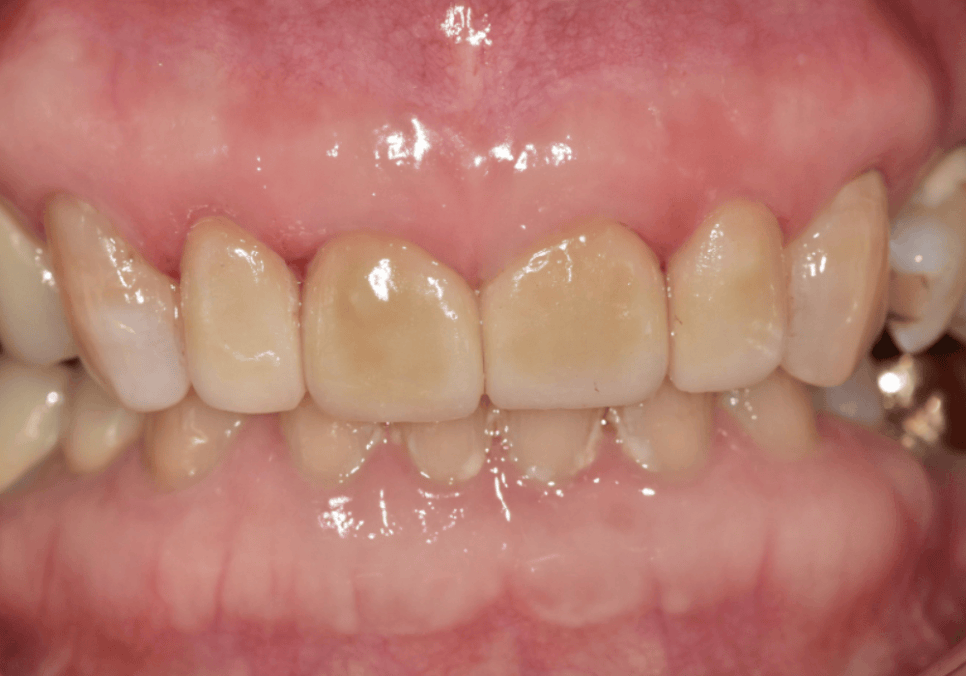

250304(전) 250318(후)

이번 70대 환자분도

이 과정을 통해

과개교합에서 오는 힘을 분산시키면서도

왜소치와 벌어진 앞니를 자연스럽게 정리하는

맞춤 라미네이트를 완성할 수 있었습니다.

250318

환자분께서도 이제 환하게 웃을 수 있다며

좋아하셨습니다.